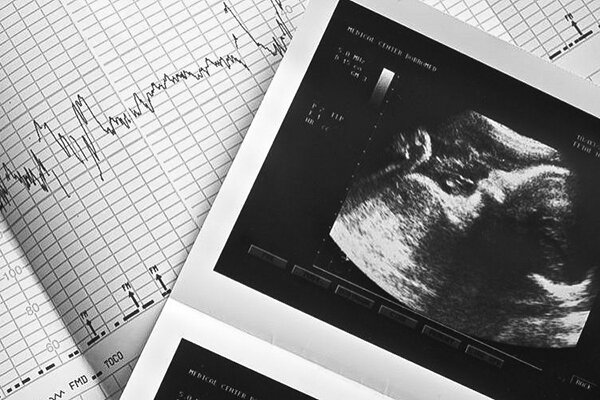

مرضیه وحید دستجردی با پرداختن به موضوع غربالگری گفت: انتخابتو و به نقل از پایگاه اطلاع رسانی دولت، غربالگری امروز در کشور ما انجام می شود و منعی برای این کار وجود ندارد.

وی با تاکید بر اینکه البته عده ای سعی کردند در قانون منع ایجاد کنند، افزود: با پیگیری های انجام شده توسط متخصصان زنان این اتفاق نیفتاد و غربالگری همچنان انجام می شود و حتی در قانون وجود دارد؛ اما در صورت عدم رعایت قوانین و مقررات مربوط به این امر، این امر محقق نشد. بنابراین منعی برای این موضوع در نظر گرفته نشده و غربالگری در کشور در حال انجام است.